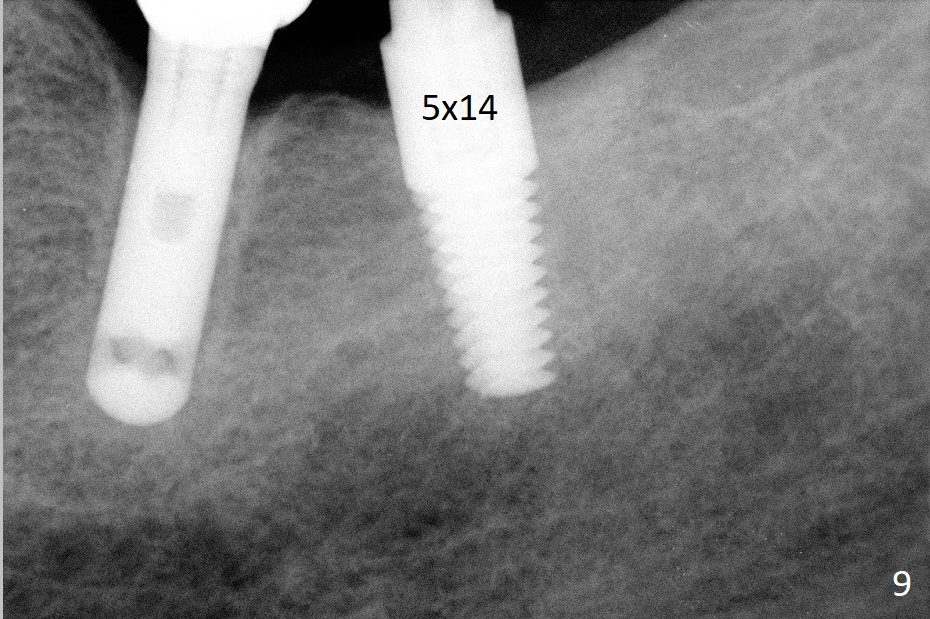

A 69-year-old man needs an implant at #18 (Fig.1,2 CT (sagittal and coronal sections)). In spite of use of surgical stent, the trajectory is not ideal (Fig.3-5). The following day the implant is removed with bone graft (Fig.6). In the 2nd placement, the trajectory is adjusted in each step (Fig.7-9 arrows) with long term stability (Fig.10,11).